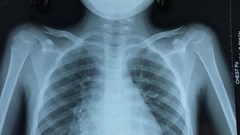

VHO- Chiều ngày 11.12, Thủ tướng Chính phủ Nguyễn Xuân Phúc đã đến thăm Bệnh viện Quân Y 175 TP.HCM. Tại đây Thủ tướng nhấn mạnh: Bệnh viện Quân Y 175 cần tiếp tục nâng cao chất lượng dịch vụ, làm tốt công tác quân, dân y kết hợp, phát triển khoa học kỹ thuật công nghệ cao, hội nhập quốc tế sâu rộng, nâng cao trình độ, tay nghề đội ngũ bác sĩ.